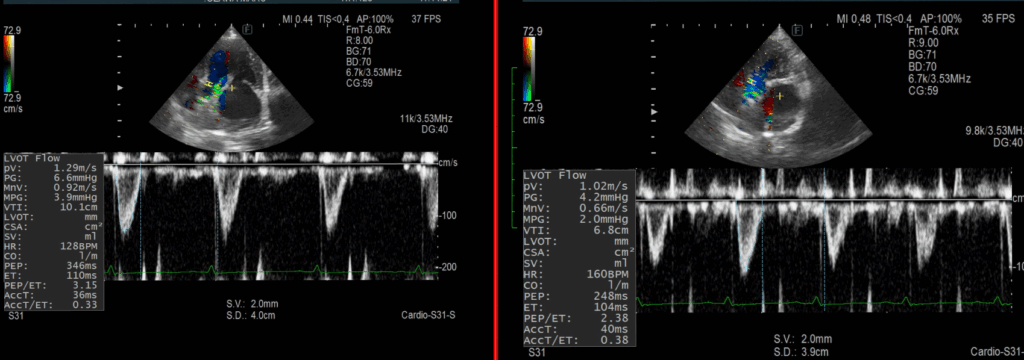

エコー画像は←が治療後で→が治療前です。

・三尖弁逆流の低下

本例は2群の肺高血圧症が疑われる状況です。

僧帽弁閉鎖不全症が重症化すると肺から左心に血流が流れづらくなります。その結果三尖弁逆流が生じます。

左心不全に対する治療強化で三尖弁逆流が低減しています。

・大動脈血流の改善

血流速波形の面積であるVTIは単位時間あたり血液がどのくらい動いたのかという指標です。

同一症例の血管径が短期間に大きく変化することはほとんどないため、血流量の指標になります。

大動脈血流のVTIが6.8cmから10.1cmに改善しています。